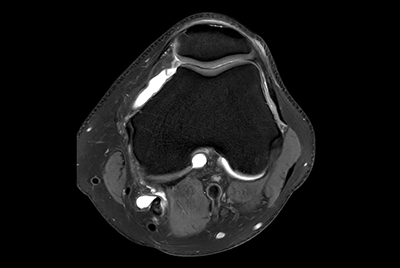

Push-button Knee exam, under 5 minutes